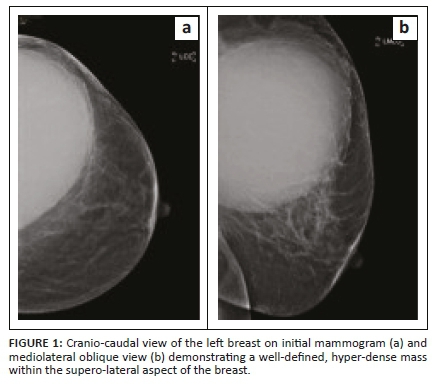

She was then referred to the radiology department for a mammogram and a breast ultrasound. The left mammogram demonstrated a 126 mm × 110 mm, circumscribed, round mass within the upper outer quadrant. The mass was homogenous with mass effect on the adjacent glandular tissue as displayed in Figures 1a and 1b. Ultrasound of the left breast demonstrated a large anechoic mass with septations and an irregular inner thickened wall with debris as displayed in Figures 2a and 2b. The right mammogram and ultrasound were within normal limits. The mass was classified as a Breast Imaging-Reporting and Data Systems (BI-RADS) 4A lesion and the patient was referred back to the surgeons. An image-guided biopsy was not performed at this stage because the patient was awaiting histology results for the biopsy performed by the surgeon.